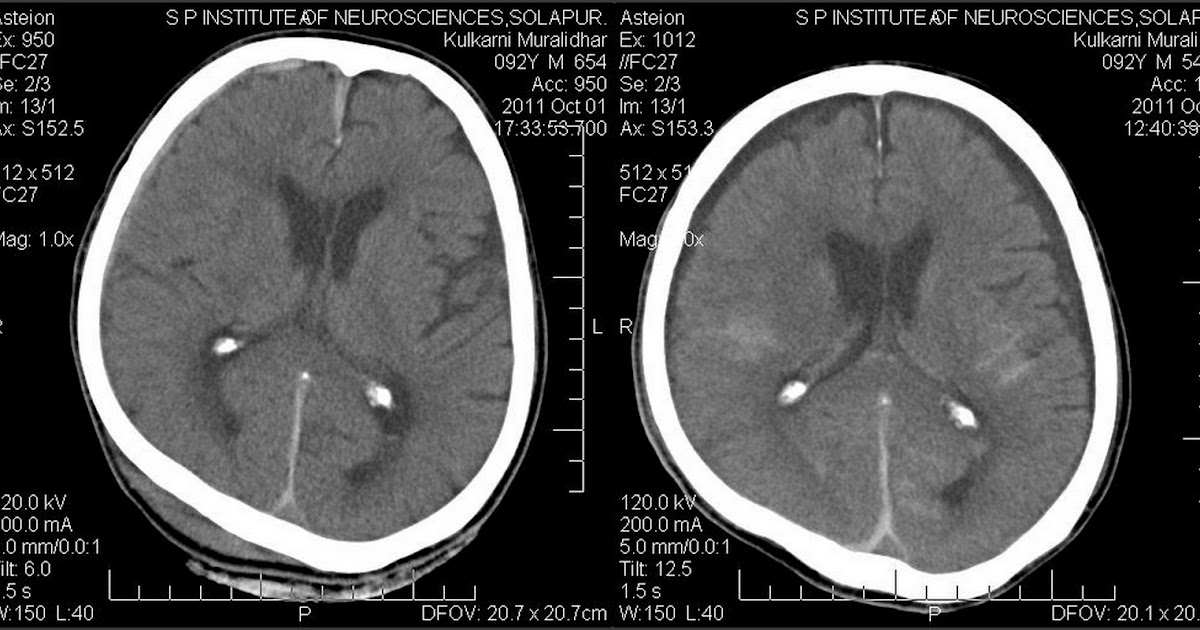

Zystische Hygrome sind gutartige Läsionen und können bei einem Patienten über lange Zeit asymptomatisch bleiben.Im Folgenden werden die wichtigsten Behandlungen, die der Hund mit Hygromen erhält, kurz vorgestellt, wobei insbesondere die Arbeit einiger Autoren hervorgehoben wird .b Schmalbandige frische Subduralhämatome temporal rechts (Pfeile). Mittels MRT meist abgrenzbar (keine Blutabbauprodukte).1 Computertomographie. Die Behandlung von Hygrom kann konservativ und operativ sein.Jack Kevorkian.

Inhaltsverzeichnis Anzeigen.a Deutliche bifrontale Hygrome (Sterne) und schmalbandiges frisches Subduralhämatom fron- tal rechts (Pfeil). Dieses Verfahren beinhaltet das Tragen von Clans – Klebebänder aus elastischem Stoff.

4 Diagnose & Krankheitsverlauf. Die Behandlung sollte nicht später als 48 Stunden nach der Verletzung erfolgen. Das Lipom selbst wird durch ein rundes und dichtes Neoplasma dargestellt, das meistens nicht .Symptome eines Hygroms am Finger.Klassische unkomplizierte subdurale Hygrome enthalten ausschließlich Liquor, weisen keine Membranen auf und zeigen kein Kontrastmittel-Enhancement.Als Behandlung verwendet chirurgische Medizin, das heißt, Chirurgie Hygrome zu entfernen, Drogenbehandlung mit Antibiotika und Medikamenten und alternative Medizin Methoden, die auf Kräutern und natürlichen Rezepten für die Behandlung basieren. Infiltration von Anästhetika an der Inzisionsstelle und an den Tumorrändern. Konservative Behandlung besteht darin, die Formation zu punktieren .